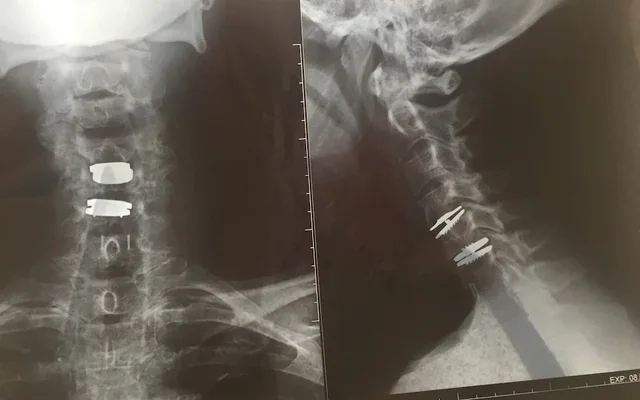

Në 2003, kur ishte 50 vjeçe, Fay kërkoi ndihmë për një nerv të dëmtuar në krah. Ajo vendosi të bëjë operacion privat me Eljamel, i cili atëherë ishte një neurokirurg i njohur dhe këshilltar qeveritar. Operacioni nuk shkoi si duhet dhe ajo u tha se do t’i duhej një ndërhyrje tjetër. Gjatë tetë viteve të ardhshme, Eljamel e operoi gjashtë herë të tjera, shumica operacione të panevojshme ose të dështuara, duke përfshirë vendosjen gabim të implanteve në shtyllën kurrizore. Operacioni i fundit në 2011 shkaktoi dëmtime të mëtejshme të nervave, përcjell dritare.net